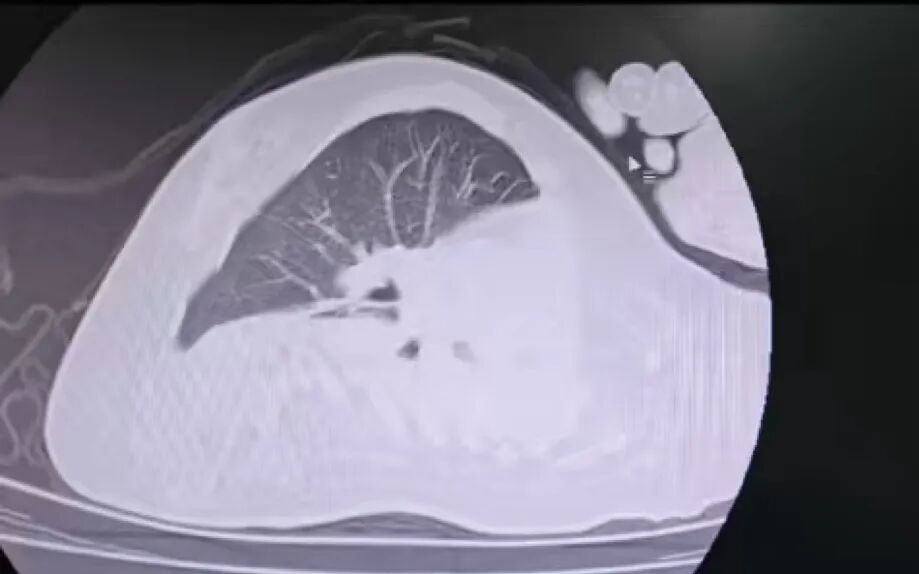

治療前

該患兒因患脊髓性肌萎縮癥長(zhǎng)期臥床,呼吸肌已嚴(yán)重?zé)o力,自主呼吸微弱且?guī)缀鯁适Э人耘盘的芰?,此次并發(fā)支氣管肺炎后,肺部感染迅速加重,生命已然懸于一線。更棘手的是,嚴(yán)重的脊柱側(cè)彎使患兒胸廓畸形、氣道解剖結(jié)構(gòu)明顯移位,常規(guī)纖支鏡進(jìn)鏡路徑完全失效,扭曲狹窄的氣道如同縱橫交錯(cuò)的“迷宮”,每一步操作都必須精準(zhǔn)到毫米級(jí)別。